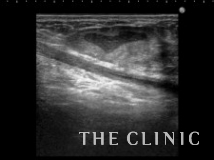

他院でヒアルロン酸豊胸を行った方ですが、炎症のためヒアルロン酸の周囲に非常に厚い被膜が形成され、瘢痕化していました。

しこりは両側の乳房全体にあり、一部は以前ヒアルロニダーゼで吸引しました。

被膜は肥厚して中心にわずかにヒアルロン酸があります。

ヒアルロニダーゼで溶解して吸引しましたが、被膜は残存しています。

エコーとの比較です。

このしこりは内腔がありヒアルロン酸がありました。

ヒアルロン酸注入によるしこりのエコー診断カルテ